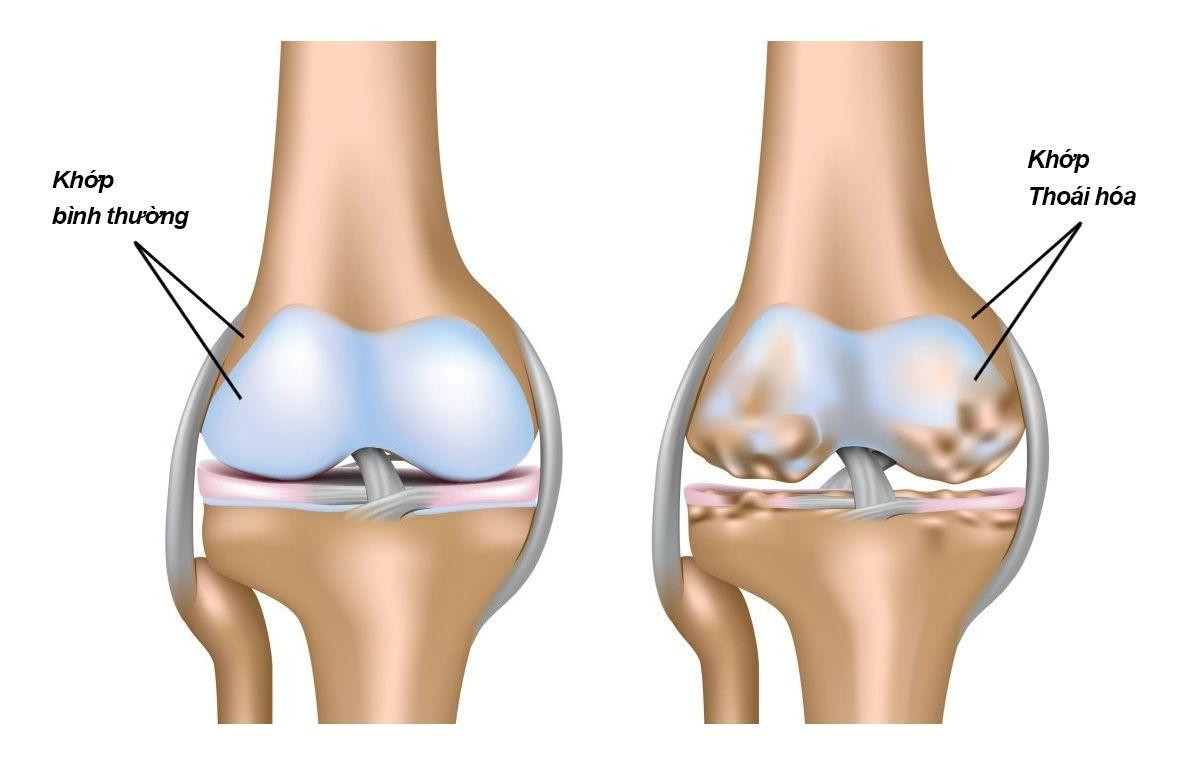

|

| Thiếu hụt chất nền sụn khớp là nguyên nhân sâu xa gây thoái hoá xương khớp |